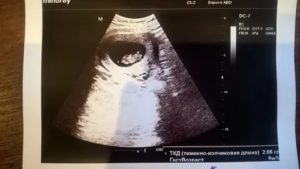

УЗИ: 10 недель беременности

Как правило, 10 неделя беременности не является сроком для проведения планового УЗИ. Но если по какой-либо причине (к примеру: уточнение срока или контроль беременности) УЗИ проводится на десятой неделе, то вас ожидает встреча с необыкновенным чудом!

Попросите врача сделать фото УЗИ 10 недель беременности, где хорошо заметно, что размеры будущего малыша на этом сроке можно сравнить с размером средней сливы. И хотя плоду еще так мало времени, но он уже напоминает настоящего крохотного человечка.

Что происходит на 10 неделе беременности?

С помощью УЗИ вы увидите четко проступающее очертание тельца своего малютки, хорошо различимы его миниатюрные ручки и ножки, заметны даже локотки и лодыжки крохи!

Этот маленький обитатель вашего живота может самостоятельно втягивать губки, выплевывая и заглатывая околоплодную жидкость, закрывает и открывает свой ротик. Малыш уже может махать согнутыми в локотках ручками, разгибать маленькие кулачки, передвигать и подгибать под себя ножки.

Представьте, сколько всего интересного и удивительного сможет узнать и увидеть при ультразвуковом исследовании мамочка на 10 неделе беременности!